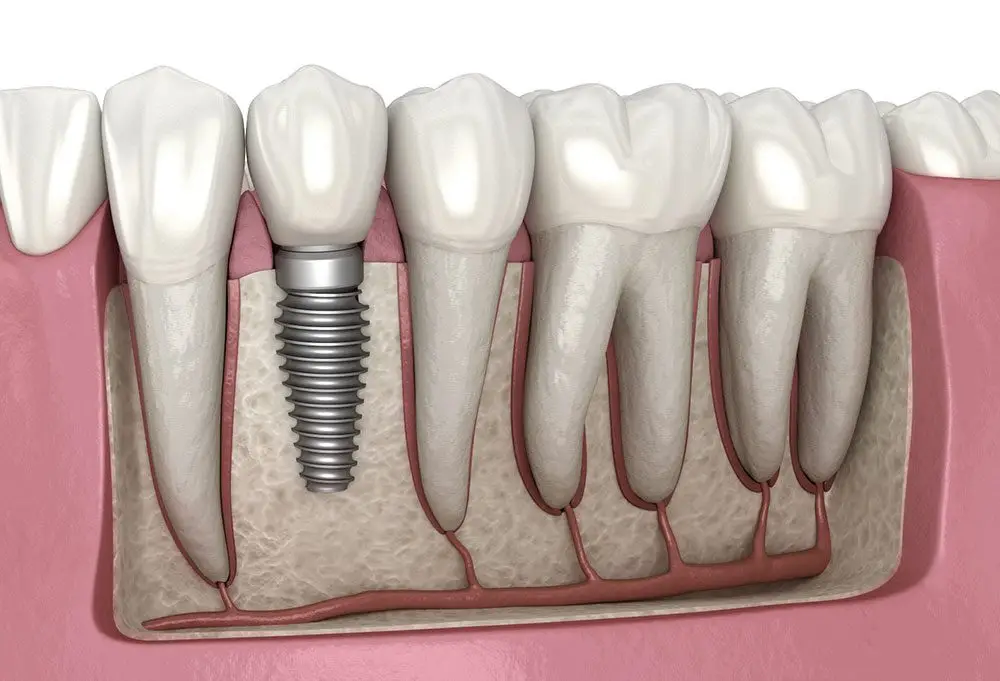

The Gold Standard for Tooth Replacement: Dental Implants in Sector 70 Noida

For residents seeking a durable, long-term solution to missing teeth, dental implants represent the most advanced and effective treatment available today. If you are struggling with ill-fitting dentures or are looking for a reliable, permanent alternative to a gap in your smile, our clinic provides world-class implantology right here in Sector 70, Noida.

Unlike traditional bridges or removable dentures, a dental implant acts as an artificial tooth root, which is surgically placed into the jawbone. This implant then permanently fuses with the bone through a process called osseointegration. This critical integration prevents the bone loss (resorption) that naturally occurs after tooth extraction, thereby preserving your facial structure and preventing a sunken appearance. For patients commuting from Sector 122 or Sector 73, the short, easy trip to our clinic is an investment in a lifetime of confidence and function.

The implant procedure is highly specialized, and we utilize state-of-the-art 3D imaging (Cone Beam Computed Tomography – CBCT) to meticulously plan the precise angle and location of the implant placement. This ensures optimal stability and minimizes recovery time. We offer various implant solutions, including single-tooth implants, implant-supported bridges, and specialized All-on-4 or All-on-6 techniques for full arch rehabilitation. If you are considering affordable dental implants in Sector 70, contact our Family Dental Clinic for a detailed consultation. We prioritize patient comfort and long-term success, making us the top choice for advanced tooth replacement in this part of Noida. Our goal is to restore not just your tooth, but your complete quality of life.